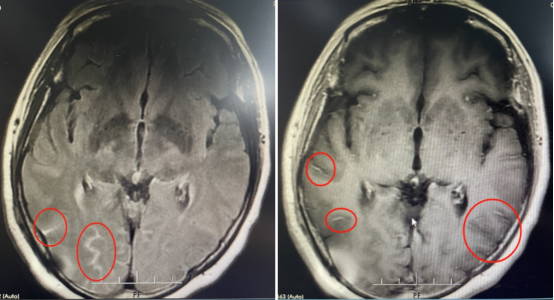

經(jīng)過檢查

原來導(dǎo)致她頭痛的根本不是頸椎病

而是患上了隱球菌腦膜炎

廣東三九腦科醫(yī)院神經(jīng)內(nèi)一科副主任匡祖穎:她的顱內(nèi)壓增高,不但導(dǎo)致對(duì)旁邊的腦組織進(jìn)行擠壓,同時(shí)引起在腦袋里形成比較長的顱神經(jīng)損傷,包括視力的下降、聽力的損傷等一系列不可逆的神經(jīng)損傷。